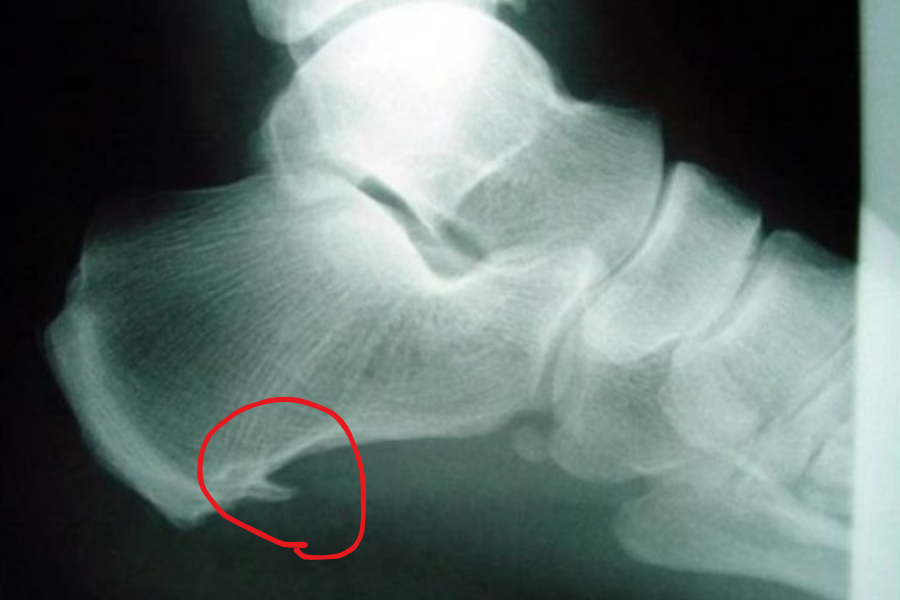

Topuk dikeni röntgen görüntüsü(topuk dikeni resmi). soldaki sağlıklı bir topuk resmi . sağdaki ise topuk dikeni oluşmuş bir topuk

Bununla birlikte topuk dikeni röntgen görüntülemede görebilirsiniz. Hemen topuğun ön kısmında küçük bir kemik çıkıntısı olarak karşımıza çıkar.

Topuk dikeni resmi, topuk dikeni röntgen görüntüsü. hemen topuğun iç ön kısmında bir kemik çıkıntı olarak görebilirsiniz